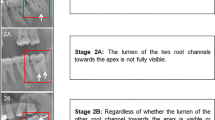

Pinchi V, Pradella F, Buti J, Baldinotti C, Focardi M, Norelli G-A (2015) A new age estimation procedure based on the 3D CBCT study of the pulp cavity and hard tissues of the teeth for forensic purposes: a pilot study. J Forensic Legal Med 36:150–157. https://doi.org/10.1016/j.jflm.2015.09.015